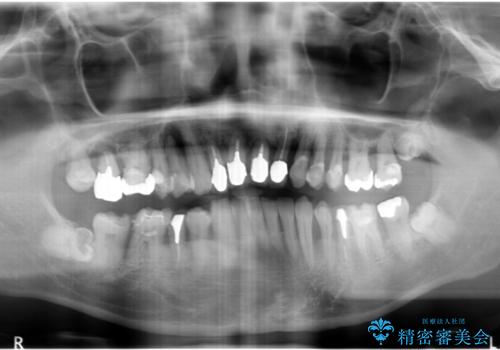

インプラント・ブリッジ補綴を含む、歯周病全顎治療

- 歯が全体的に揺れ始め、恐怖を感じ他院に相談に行ったところ、全体的な歯周病の問題・抜歯の必要性・入れ歯の提案を受け、入れ歯以外の選択肢を希望され来院されました。

全体的な歯周病検査を行い、多数の残すことのできない抜歯の必要な歯を認めたため、残せる歯に対しての徹底的な歯周病治療、失った歯に対しブリッジ・インプラント治療を全顎的に行っていくこととしました。

長期間にわたる治療後、歯に対する意識も大きく変わりプラークコントロールも非常に良くなりました。